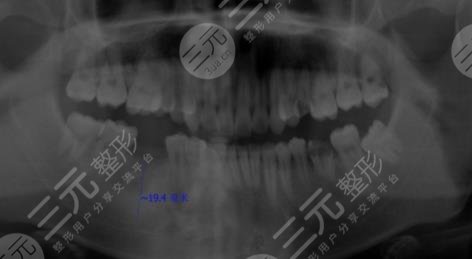

因?yàn)槲艺娴氖窒矚g吃糖,也就是很喜歡甜食,幾乎每天都有很多的糖攝入,有的時(shí)候連吃米飯我想要吃甜的,這就導(dǎo)致了我的年紀(jì)輕輕牙齒就蛀了,因?yàn)樘浅远嗔?,剛開始的時(shí)候還只是進(jìn)行補(bǔ)牙,但是隨著時(shí)間越來(lái)越久,我的牙齒的孔洞越來(lái)越大,然后沒(méi)有辦法就是拔掉了,我想著一直去補(bǔ)也不是問(wèn)題,就跟父母商量之后,來(lái)到了鎮(zhèn)江口腔醫(yī)院進(jìn)行種植牙。

醫(yī)生看了我的牙齒情況之后,為我判斷了幾顆比較需要進(jìn)行種植牙的地方進(jìn)行了拔除。大概在拔完牙,一星期后我進(jìn)行了種植牙,剛種上的時(shí)候還是覺(jué)得挺不舒服的,但是隨著時(shí)間的推移,我逐漸適應(yīng)了自己的種植牙,并且種植的牙齒比之前更加潔白,它不單單解決了我的口腔問(wèn)題,還讓我整個(gè)人的氣質(zhì)都上升了不少呢。